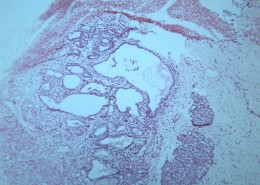

首页 > 其他类别 > 畸胎瘤(12张) > 畸胎瘤 第3张

畸胎瘤 - 第3张

第 3 / 12 张

猫扑风铃上传畸胎瘤 图集中 / 共有 12 张图片